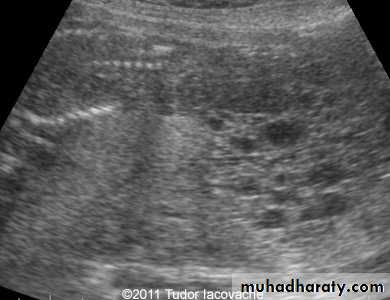

US of PCOSPCOS

In PCOS monophasic follicles